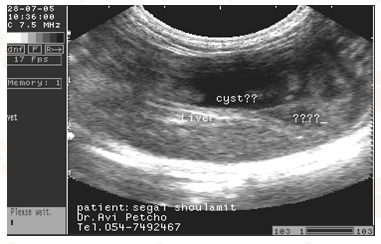

החתולה בבה אבדה מחיוניותה מזה מספר חודשים. כבר שנתיים שהיא מקיאה לסירוגין , מרזה ונחבאת אל הכלים. אם הגעתה למרפאה הוטרינרית נראה שהמצב אינו מעודד. בדיקות הדם הראו תפקוד כבד לקוי ולאחר בדיקת האולטראסאונד הובהר הגרוע מכל:

חשד לגידול של הכבד – כיס המרה – הלבלב או של כולם. קשה מאד ל"הפריד" ע"י הדמיה תהליך פתולוגי במיוחד אם הוא נוגע ללבלב או לצינור כיס המרה המשותף. הדמיית המעי הדק (תריסריון) גם היא קשה והאבחנה הסופית ניתנת לביצוע רק בעזרת הדמיה ויזואלית היינו פתיחת בטן.